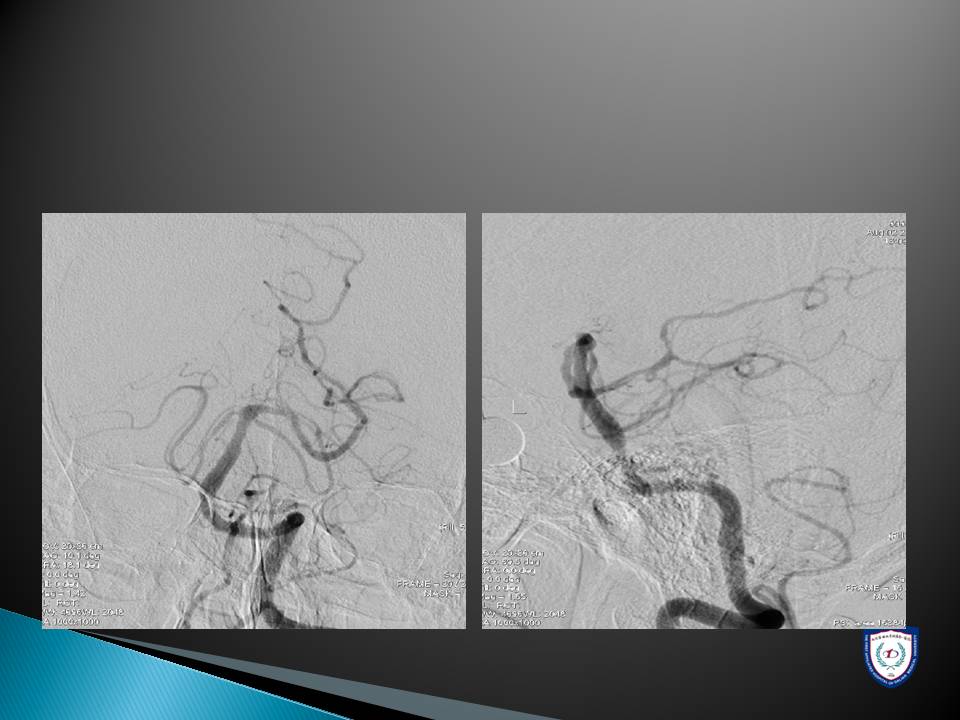

心房颤动导致的脑卒中和外周动脉栓塞的介入治疗